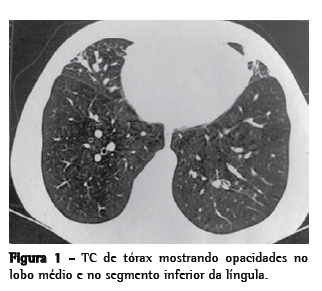

Como persistia a tosse, foi realizada TC de tórax, que evidenciou opacidades em lobo médio, segmento inferior da língula e segmento anterior do lobo superior direito, assim como espessamento das bainhas peribrônquicas, e sinais de impactação mucoide (Figura 1). Em seguida, nova fibrobroncoscopia foi realizada, demonstrando que uma grande quantidade de muco amarelado difuso persistia, e a análise microbiológica revelou o crescimento de Staphylococcus aureus (50.000 UFC/mL).

A TCAR é o melhor exame de imagem para o diagnóstico de pneumonia lipoide, revelando consolidações alveolares, opacidades em vidro fosco, lesões nodulares e espessamento de septos interlobulares e do interstício intralobular.(5) No caso clínico em questão, as alterações da TC de tórax, ainda que associadas às alterações clínicas, não foram suficientes para a conclusão diagnóstica. Prosseguiu-se a investigação, com a análise microbiológica do lavado broncoalveolar, sendo encontrado S. aureus mesmo após o tratamento com ciprofloxacina por 21 dias, e a paciente permaneceu sintomática. A presença de óleo nos pulmões pode predispor a pneumonias recorrentes e, inclusive, a infecções por germes atípicos.(12)